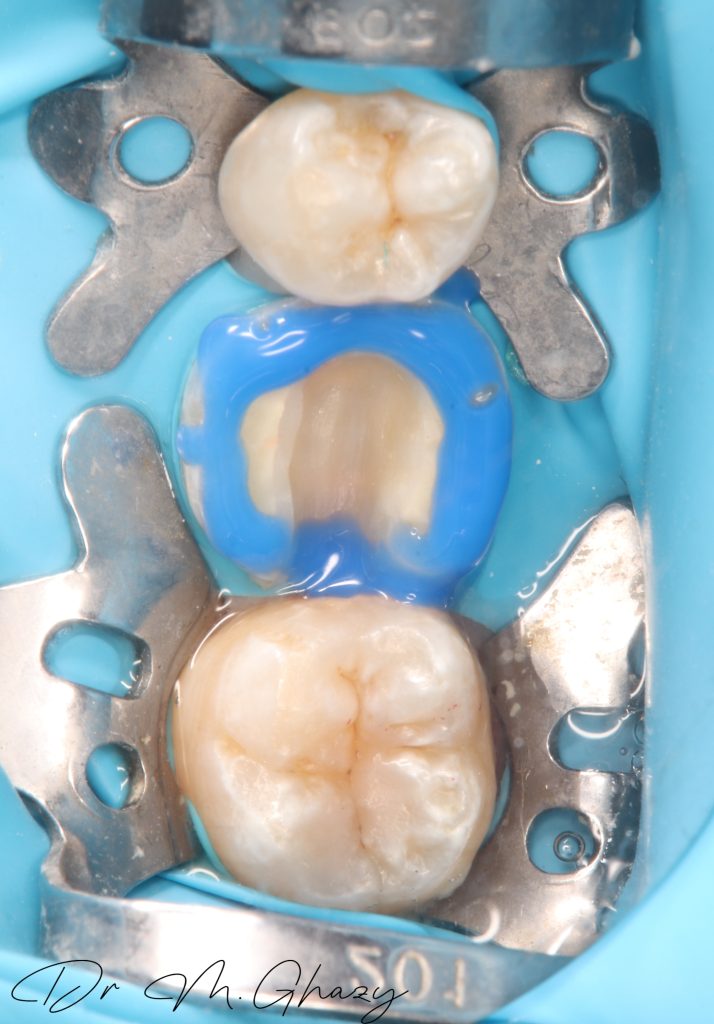

Occlusal reduction and cavity optimization done

Isolation

Selective acid etching